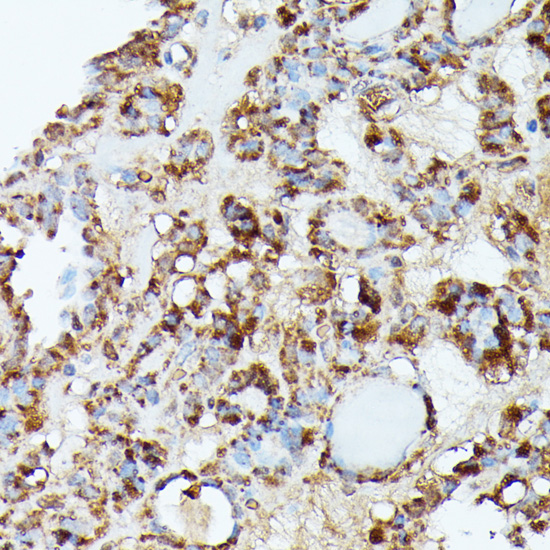

Immunohistochemistry of paraffin-embedded rat heart using NUBP1 antibody at dilution of 1:100 (40x lens).

Immunohistochemistry of paraffin-embedded human thyroid cancer using NUBP1 antibody at dilution of 1:100 (40x lens).

Immunohistochemistry of paraffin-embedded human colon carcinoma using NUBP1 antibody at dilution of 1:100 (40x lens).

Immunohistochemistry of paraffin-embedded mouse liver using NUBP1 antibody at dilution of 1:100 (40x lens).

Immunohistochemistry of paraffin-embedded mouse kidney using NUBP1 antibody at dilution of 1:100 (40x lens).

IHC 1:50 - 1:200